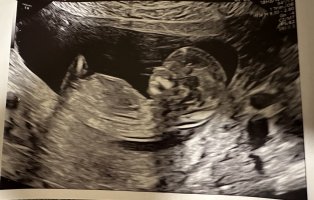

Åå, så kjedelig med dårlige bilder :/.. Jeg har dette også, men her ser man heller ikke stort. Jordmor sa ingenting om hva hun trodde eller noe som helst om kjønnet..Disse bildene var veldig dårlig til å være 14 uker. har du flere fra denne eller tidligere? burde være lett å se kjønn når man er så langt på vei. det på bilde nr 1 er ikke nub, det er en del av benet som har kommet med på bildet. Jeg tror det er jente da det ville vært veldig synlig i uke 14 om det var gutt. Ser og lang hvit strek på flere av bildene som samsvarer med jentenub.

? Er 13+1 her